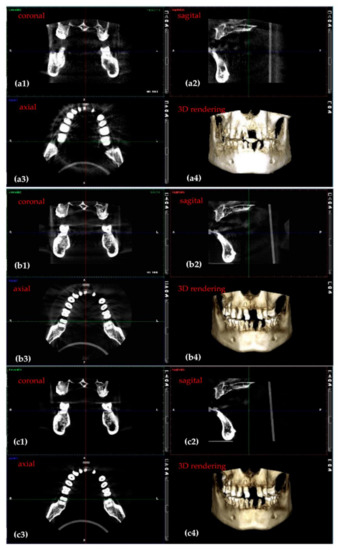

3.3. Application of the Optimization Protocol on Patients (In Vivo)

3.4. Differences Between the Planmeca and the Soredex System